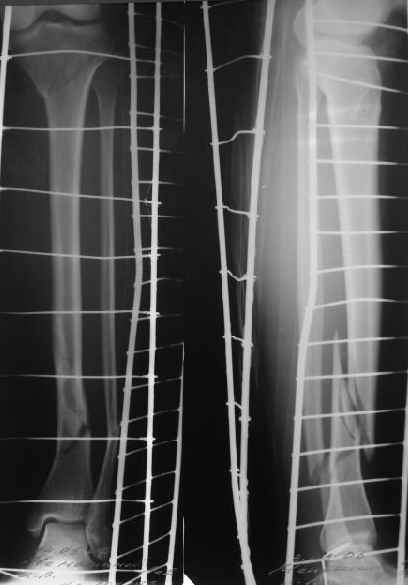

A typical case is attached, also an image with intra-op reduction obtained by a small wire distractor, in the moment of insertion a Poller wire in AP direction. Fixation by a SIGN nail. Despite the fibula was not fixed healing was obtained with the unchanged alignment.

Сделали все-таки стержнем. На всякий случай просверлил дополнительное проксимальное отверстие, так что получилось три 45-градусных винта.

В дистракторе провеи спиц поболше в прокисмальном отделе, чтобы не разобщить фрагменты при сгибании колена. Комментарии и критика приветствуются.

We proceeded with nailing using a small wire distractor, with few wires at the proximal end to prevent displacement with forced knee flexion. Images attached. Comments and critics are welcome.

In this particlar case 4 frontal wires were inserted in anterior and posterior aspects at both sides of proximal fracture, and fixed to a single half ring with some bend to provide compression with wire tension. Image attached.

На одной опоре, расположенной чуть дистальнее обычного, были закреплены 4 спицы, проведенные во фронтальной плоскости, по 2 в передней и задней части смежных фрагментов. Закреплены так, чтобы при их натяжении создалась компрессия. Картинка в приложении.